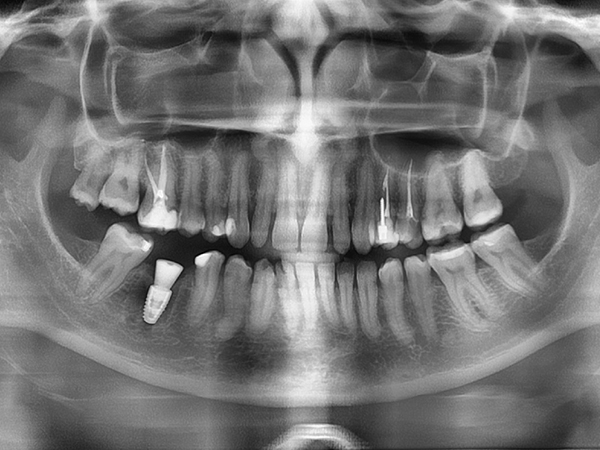

Установка имплантата Straumann BLT

ЖалобыРазрушение коронковой части зуба и воспаление

Перелечивание и ортопедическое восстановление в данном случае были невозможны — принято решение об удалении с одномоментной имплантацией. Как проходило лечение: 👇🏻

До